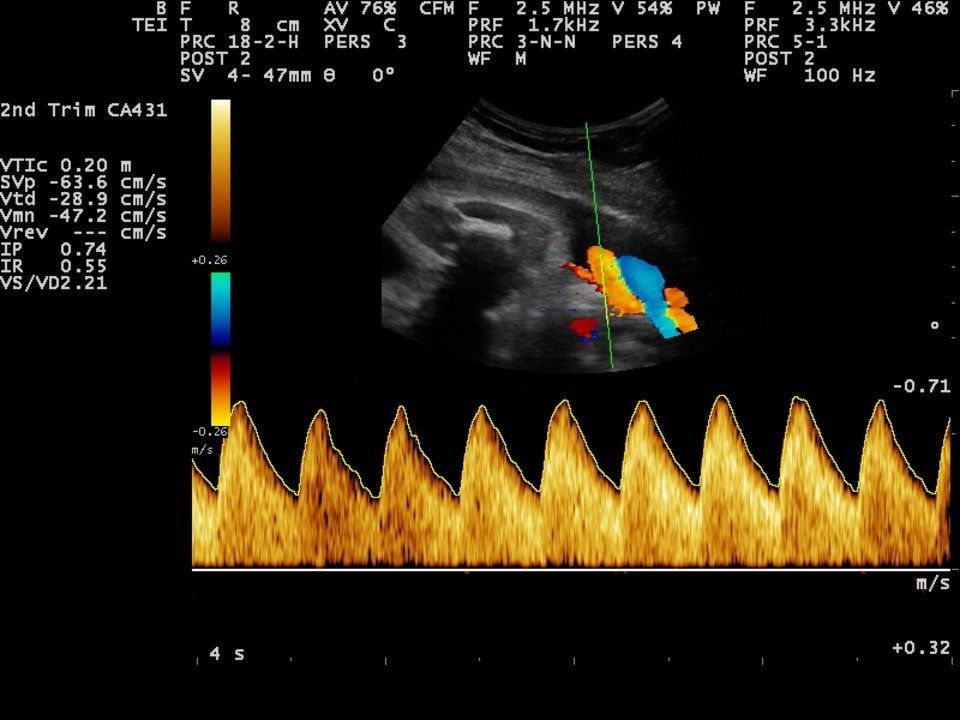

Doppler Scan

One of the main aims of routine antenatal care is to identify babies who are not thriving in the womb. It is possible that medical interventions might improve outcomes for these babies, if they can be identified. Doppler ultrasound uses sound waves to detect the movement of blood in vessels. It is used in pregnancy to studyblood circulation in the baby, uterus and placenta. Using it in high-risk pregnancies, where there is concern about the baby's condition, shows benefits.

Uterine artery Doppler scans:

Uterine arteries are the vessels which carry blood to your womb (uterus). A uterine artery Doppler scan checks that enough blood is reaching your placenta.

• Umbilical artery Doppler measurement.

• Uterine Artery Doppler measurement.